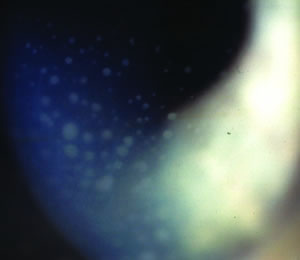

葡萄膜大腦炎-玻璃體混濁1.前驅期 又稱腦炎與腦膜炎期。常突然發病,多數有感冒症狀、全身不適、發熱 頭痛、頭暈,常伴有腦膜刺激征、嗜睡、耳鳴、聽力障礙及意識障礙,偶可見偏癱、失語、腦神經癱瘓。約有50%的患者出現耳鳴和聽力減退,常為一過性,少數可有嚴重耳聾。Vogt-小柳綜合徵,大約50%患者在起病期有腦膜刺激征,而原田綜合徵患者約有90%有腦膜刺激征症狀。此期常持續數月後逐漸緩解。

2.眼病期 一般在前驅症狀5~6天后出現眼病,雙眼可同時或先後出現瀰漫性滲出性葡萄膜炎,視力高度減退。Vogt-小柳綜合徵患者虹膜睫狀體炎明顯,角膜後壁有大小不等的角膜沉積物(KP)和虹膜結節,易引起虹膜後粘連,屈光間質渾濁。原田綜合徵患者視盤充血水腫,黃斑部水腫更明顯,後極視網膜斑狀水腫發灰,常引起視網膜脫離